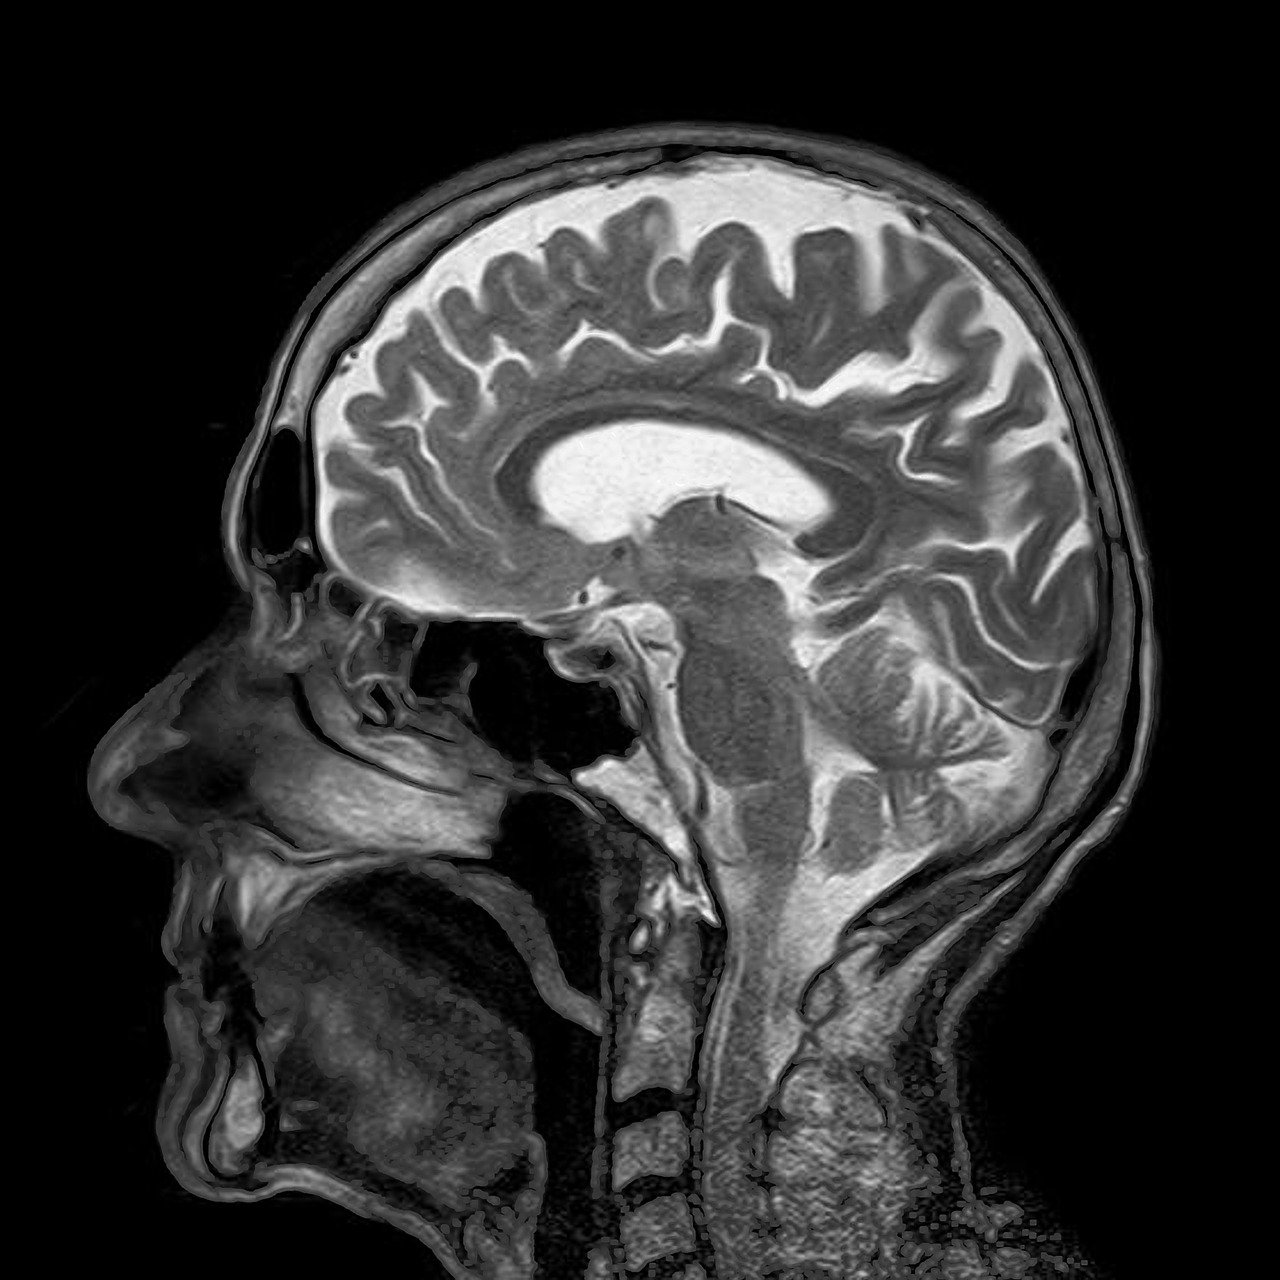

2. 기능적 자기 공명영상 (Functional MRI, fMRI)

fMRI는 뇌의 특정 부위가 활성화될 때 발생하는 산소 소비량 변화를 관찰하여, 뇌의 활동을 실시간으로 측정하는 방법입니다. 특히 감정과 관련된 연구에 유용하여, 불안, 공포, 기쁨 등 감정이 일어날 때 뇌의 반응을 관찰하는 데 많이 사용됩니다. 3. 피부전도도 (Skin Conductance Response, SCR)